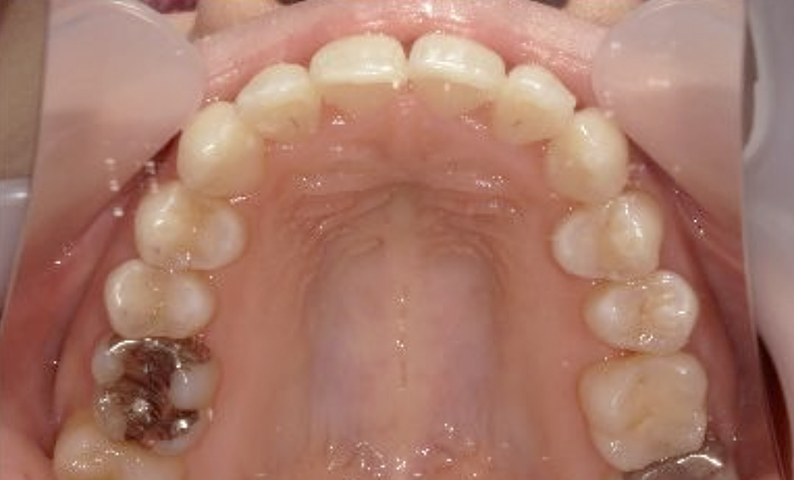

症例_023 上顎だけの部分矯正

治療期間:9ヶ月金額:30万円+税女性前歯のガタガタ上の前歯だけ

| Before | After |

|---|---|

|